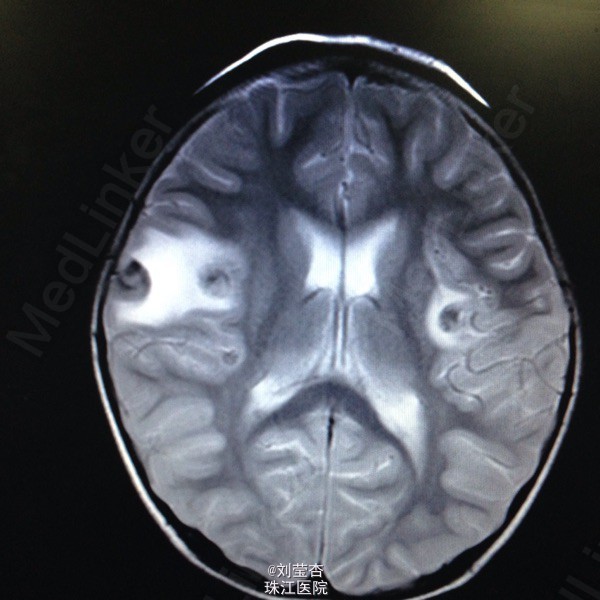

患儿女,3岁,因“咳嗽、流涕6天,发热5天,抽搐1次”入院。患儿接触家猫后出现流清涕,伴咳嗽,为间断单声咳,2天后出现发热,热峰39.5℃,予退热处理,患儿仍有反复发热,后患儿出现双眼向中上方凝视,双眼眼周肌肉抽动,伴口角流涎,无伴口周发绀、牙关紧闭,神志清楚,呼之可应,体温不详,四肢末梢温暖,四肢肌张力不高,持续约1分钟后可自行缓解。到当地医院就诊,查血常规:白细胞10.8G/L,中性粒细胞66.1%,淋巴细胞百分数27.1%,血红蛋白110g/L,血小板272 G/L,CRP4.2mg/L;胸片示支气管炎;头颅CT示右侧颞叶、双额叶多发散在脑出血。予吸氧、退热、抗感染、抗炎、补液、降颅压、止血等处理,患儿未再出现抽搐,患儿仍有反复发热,家属要求转我院进一步治疗。

查体:浅昏迷,反应一般,CRT2s,左侧耳后级颌下可触及3个肿大淋巴结,大小为0.5*0.5cm,质软,可活动,无压痛,与周围组织不粘连,双侧瞳孔等大不等圆,左侧瞳孔3mm,右侧瞳孔2.5mm,对光反射灵敏,口腔黏膜可见散在溃疡,咽部粘膜充血,双侧扁桃体Ⅰ度肿大,充血,未见黄白色脓点及分泌物,颈部稍抵抗,双肺呼吸音粗糙,可闻及大量痰鸣音,脑膜刺激症Kernig征可疑阳性,Brudzinski征可疑阳性。病毒八项:RUBE-IgG 26.8IU/Ml,CMV-IgG 117U/Ml,HSV-IgM 2.3S/CO,HSV-IgG 21.0S/CO,病毒两项:EB病毒DNA定量<5.00E+02(阳性)拷贝/mL,巨细胞病毒DNA定量9.65E+02(阳性)拷贝/mL;脑脊液常规:无色,透明,RBC 420M/L,WBC 40M/L,红细胞形态基本正常,潘氏试验(-);脑脊液单纯疱疹病毒DNA定量:单纯疱疹Ⅰ型DNA定量4.79+03(阳性)拷贝/mL,单纯疱疹Ⅱ型DNA定量低于检测下限拷贝/mL。

诊断:1.病毒性脑炎(单纯疱疹病毒感染)2.支气管肺炎。入院后予抗炎、抗病毒、抗惊厥、脱水、降颅压、促醒、输血浆,改善循环、雾化吸入、维持水电质平衡、营养支持等治疗。